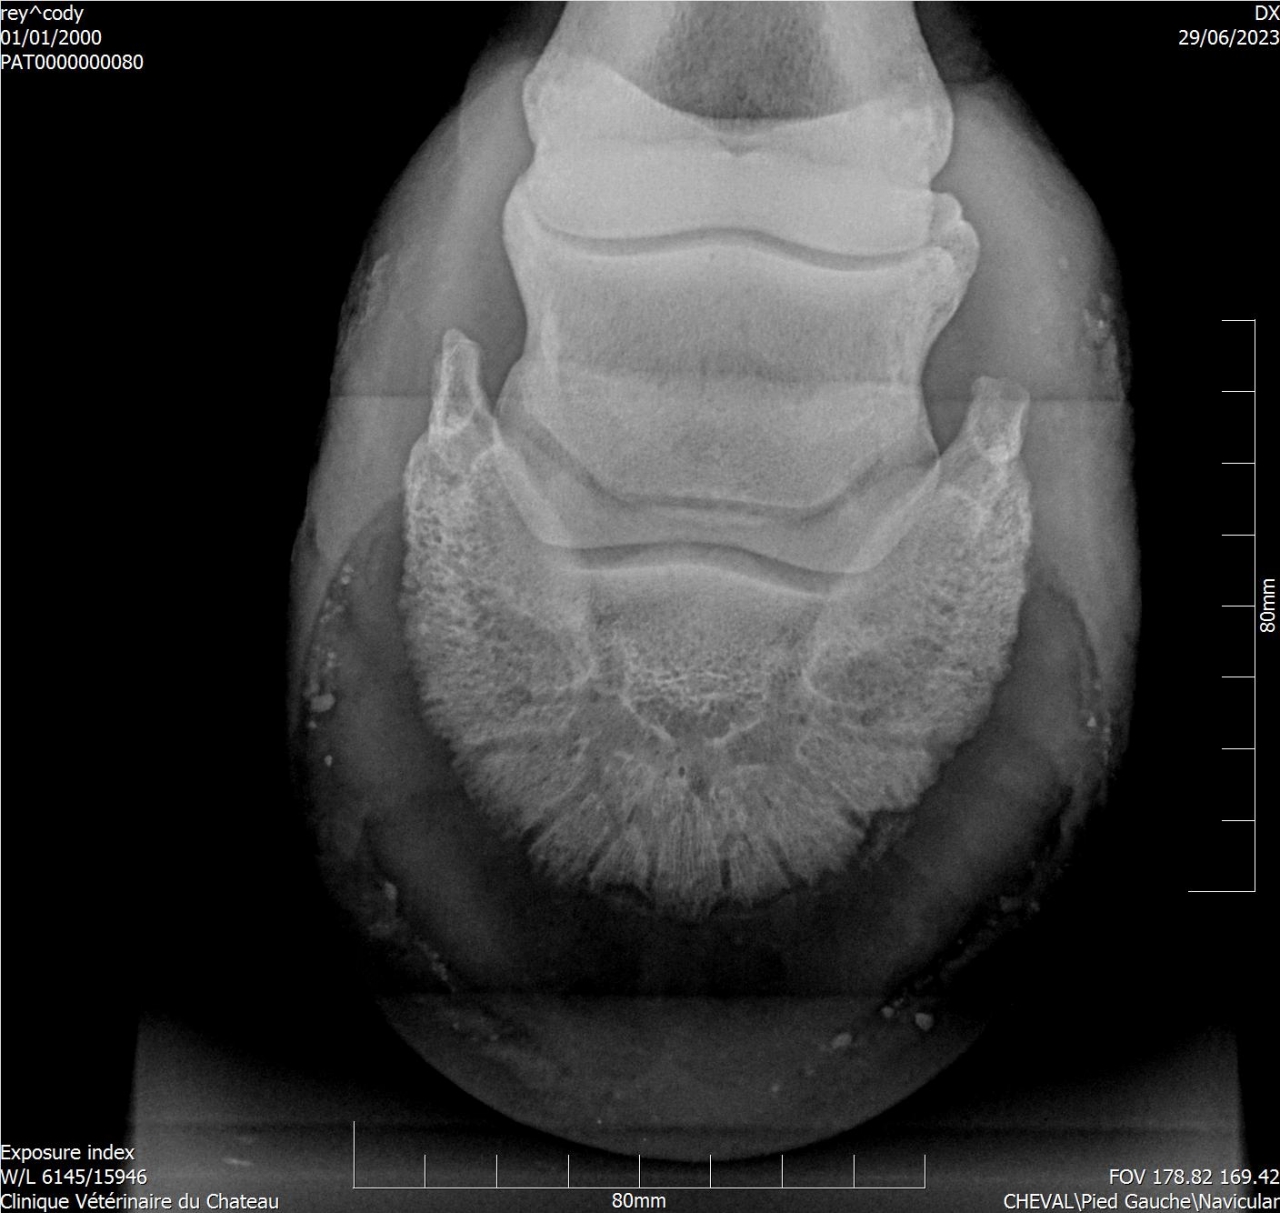

| Dire merci | Cody a une sensibilité que personne n'arrive à expliquer ... Les radios montrent une ossification des processus palmaires sur les 2 antérieurs, et une légère bascule de P3 sur l'antérieur gauche. A priori le naviculaire est correct. J'ai trouvé un maréchal-ferrant qui pose des Duplos. Vaut il mieux brocher ou coller ? |

| Dire merci | Deux personnes m'ont parlé des Duplo, les vétos ont conseillé ferrure en M ou ferrure normale ... L'année dernière Cody a été ferré avec des fers oignons et plaques en cuir, ça n'a rien changé. Ces fers ont été conseillés par le maréchal-ferrant car le véto consulté à l'époque conseillait des egg bar. Il me semble qu'avec l'ossification des processus palmaires les fers en métal n'étaient pas l'idéal. Voici les radios : ![]() ![]() ![]() ![]() J'essaye de régler les problèmes physiques pour voir si ça change quelque chose monté. Je commence par les pieds. |